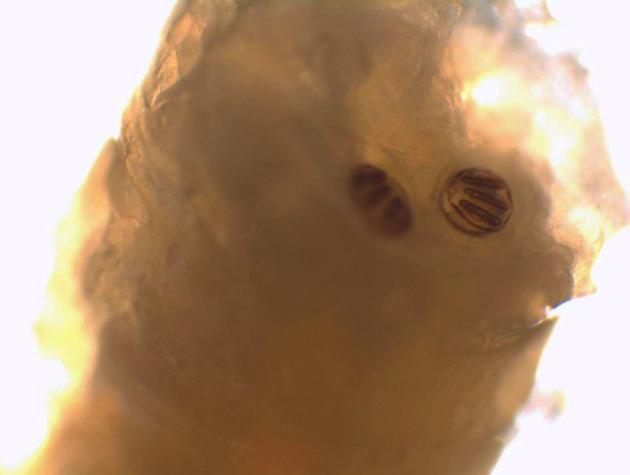

Myiasis is the infestation of living bodies of animals and humans with fly larvae or maggots. These accidental or obligatory parasites grow in three stages in the host while feeding on his tissues. Myiasis in a hospital area is a rare situation when flies accidentally lay their eggs on patients, mostly in open wounds or cavities. Case presentation. We report a case of a 72-year-old patient admitted to a general surgery department for peritonitis, then to an intensive care unit (ICU) for septic shock where he was intubated. Some maggots were seen moving in his nasal cavity a few days after his admission and were sent to our laboratory for examination. The larvae were identified as the third larval stage of sp. They were removed entirely after intense nasal washing. A checking examination of his nasal cavities revealed no evidence of further infestation. After nasal washing, no other larvae were seen but unfortunately, the patient died of septic shock a few days later.

Few cases of nasal myiasis in hospitalized patients were reported. ICU myiasis, extremely rare, is caused by the patient's inability to fend off the flies because of their conscious state, presence of blood or odors caused by infections, and the warm humid environment.